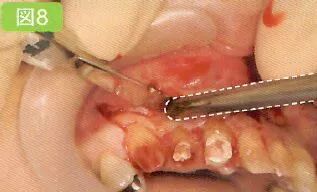

8 去除和刮治不良肉芽组织

拔牙窝最深处需要医生探头去看。所以口腔卫生士尽量要抓住医生不处于探头看的时候进行吸唾操作。有部分医生也可以独自完成治疗和吸唾的操作。

存在重度牙周病的牙齿,在其牙颈部和根尖部长有不良肉芽组织。这些不良肉芽组织会成为术后出血的诱因,因此要事先用刮匙将其彻底清除干净。

1,确认拔牙窝处是否残留了部分破损的牙冠、牙根以及碎屑。

2,确认邻牙上是否附着牙结石,是否有龋蚀。

3,刮治过程中,保证不良肉芽组织周围术野。

吸引拔牙窝。不过,拔智齿时,可能会暴露下牙槽神经。向医生确认下牙槽管是否有暴露的可能性之后,再吸引拔牙窝底部。对口腔卫生士而言必须依靠经验掌握插入吸唾器的深度。

此外,进行刮治时使用吸唾器吸引刮匙操作的区域。

刮治后,为了确认邻牙是否有牙结石附着和龋,可以使用吸唾器吸引邻在牙侧面。医生和其助手的术野是不同的。特别是较小拔牙窝,根据角度的不同,可能会导致主治医生观察时视线被阻碍。口腔卫生士在确认了是否有不良肉芽组织残留和破损牙根之后,要将自己所处角度看到的情况传达给医生。

刮治时吸引手刮匙的操作部位